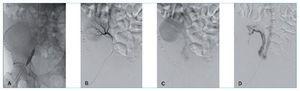

Figura 2. angioplastia con balón. A) Angioplastia con balón 12 × 40 mm de la estenosis ilíaca. B) Resultado angiográfico posterior a la angioplastia venosa, fase temprana arteriografía renal. C) Fase tardía arteriografía renal observando retorno venoso inmediato. D) Venografía directa posterior a trombolisis venosa y arterial observando restitución total del flujo anterógrado y ausencia de trombosis residual significativa.